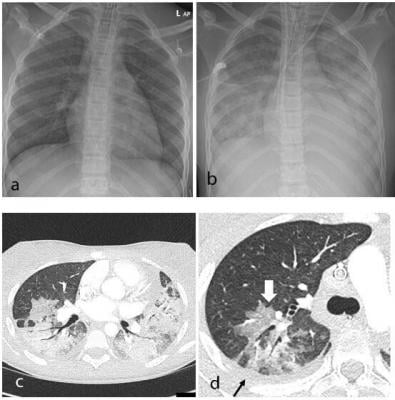

Thoracic findings in a 15-year-old girl with Multisystem Inflammatory Syndrome in Children (MIS-C). (a) Chest radiograph on admission shows mild perihilar bronchial wall cuffing. (b) Chest radiograph on the third day of admission demonstrates extensive airspace opacification with a mid and lower zone predominance. (c, d) Contrast-enhanced axial CT chest of the thorax at day 3 shows areas of ground-glass opacification (GGO) and dense airspace consolidation with air bronchograms. (c) This conformed to a mosaic pattern with a bronchocentric distribution to the GGO (white arrow, d) involving both central and peripheral lung parenchyma with pleural effusions (black small arrow, d). image courtesy of Radiological Society of North America

All 35 children underwent chest X-ray due to fever, sepsis or features of multisystem inflammation. Nineteen X-rays were abnormal, the most common finding being that of bronchial wall thickening.

The predominant findings on chest CT were basal consolidation, or part of the lung filling with fluid; and collapsed lung with pleural effusions, or build-up of fluid in the outer membranes of the lungs.